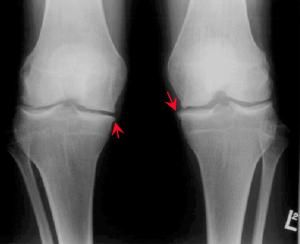

簡介

膝關節退行性關節炎臨床症狀

膝關節疼痛是膝關節退行性關節炎的主要症狀,表現為鈍痛,晨起或關節處於某一位置過久後,疼痛最為明顯,稍加活動即可減輕。但活動過多時,由於膝關節摩擦又感疼痛,氣候變化時疼痛加重。患者感到膝關節不靈活,休息後更覺明顯。膝關節出現僵硬狀態,活動時膝關節可發出粗糙的摩擦聲。這些症狀可隨著病理變化的加劇而加重。除疼痛外,局部地區腫脹、有滲液,肌肉萎縮,甚至出現關節畸形,活動受限。治療